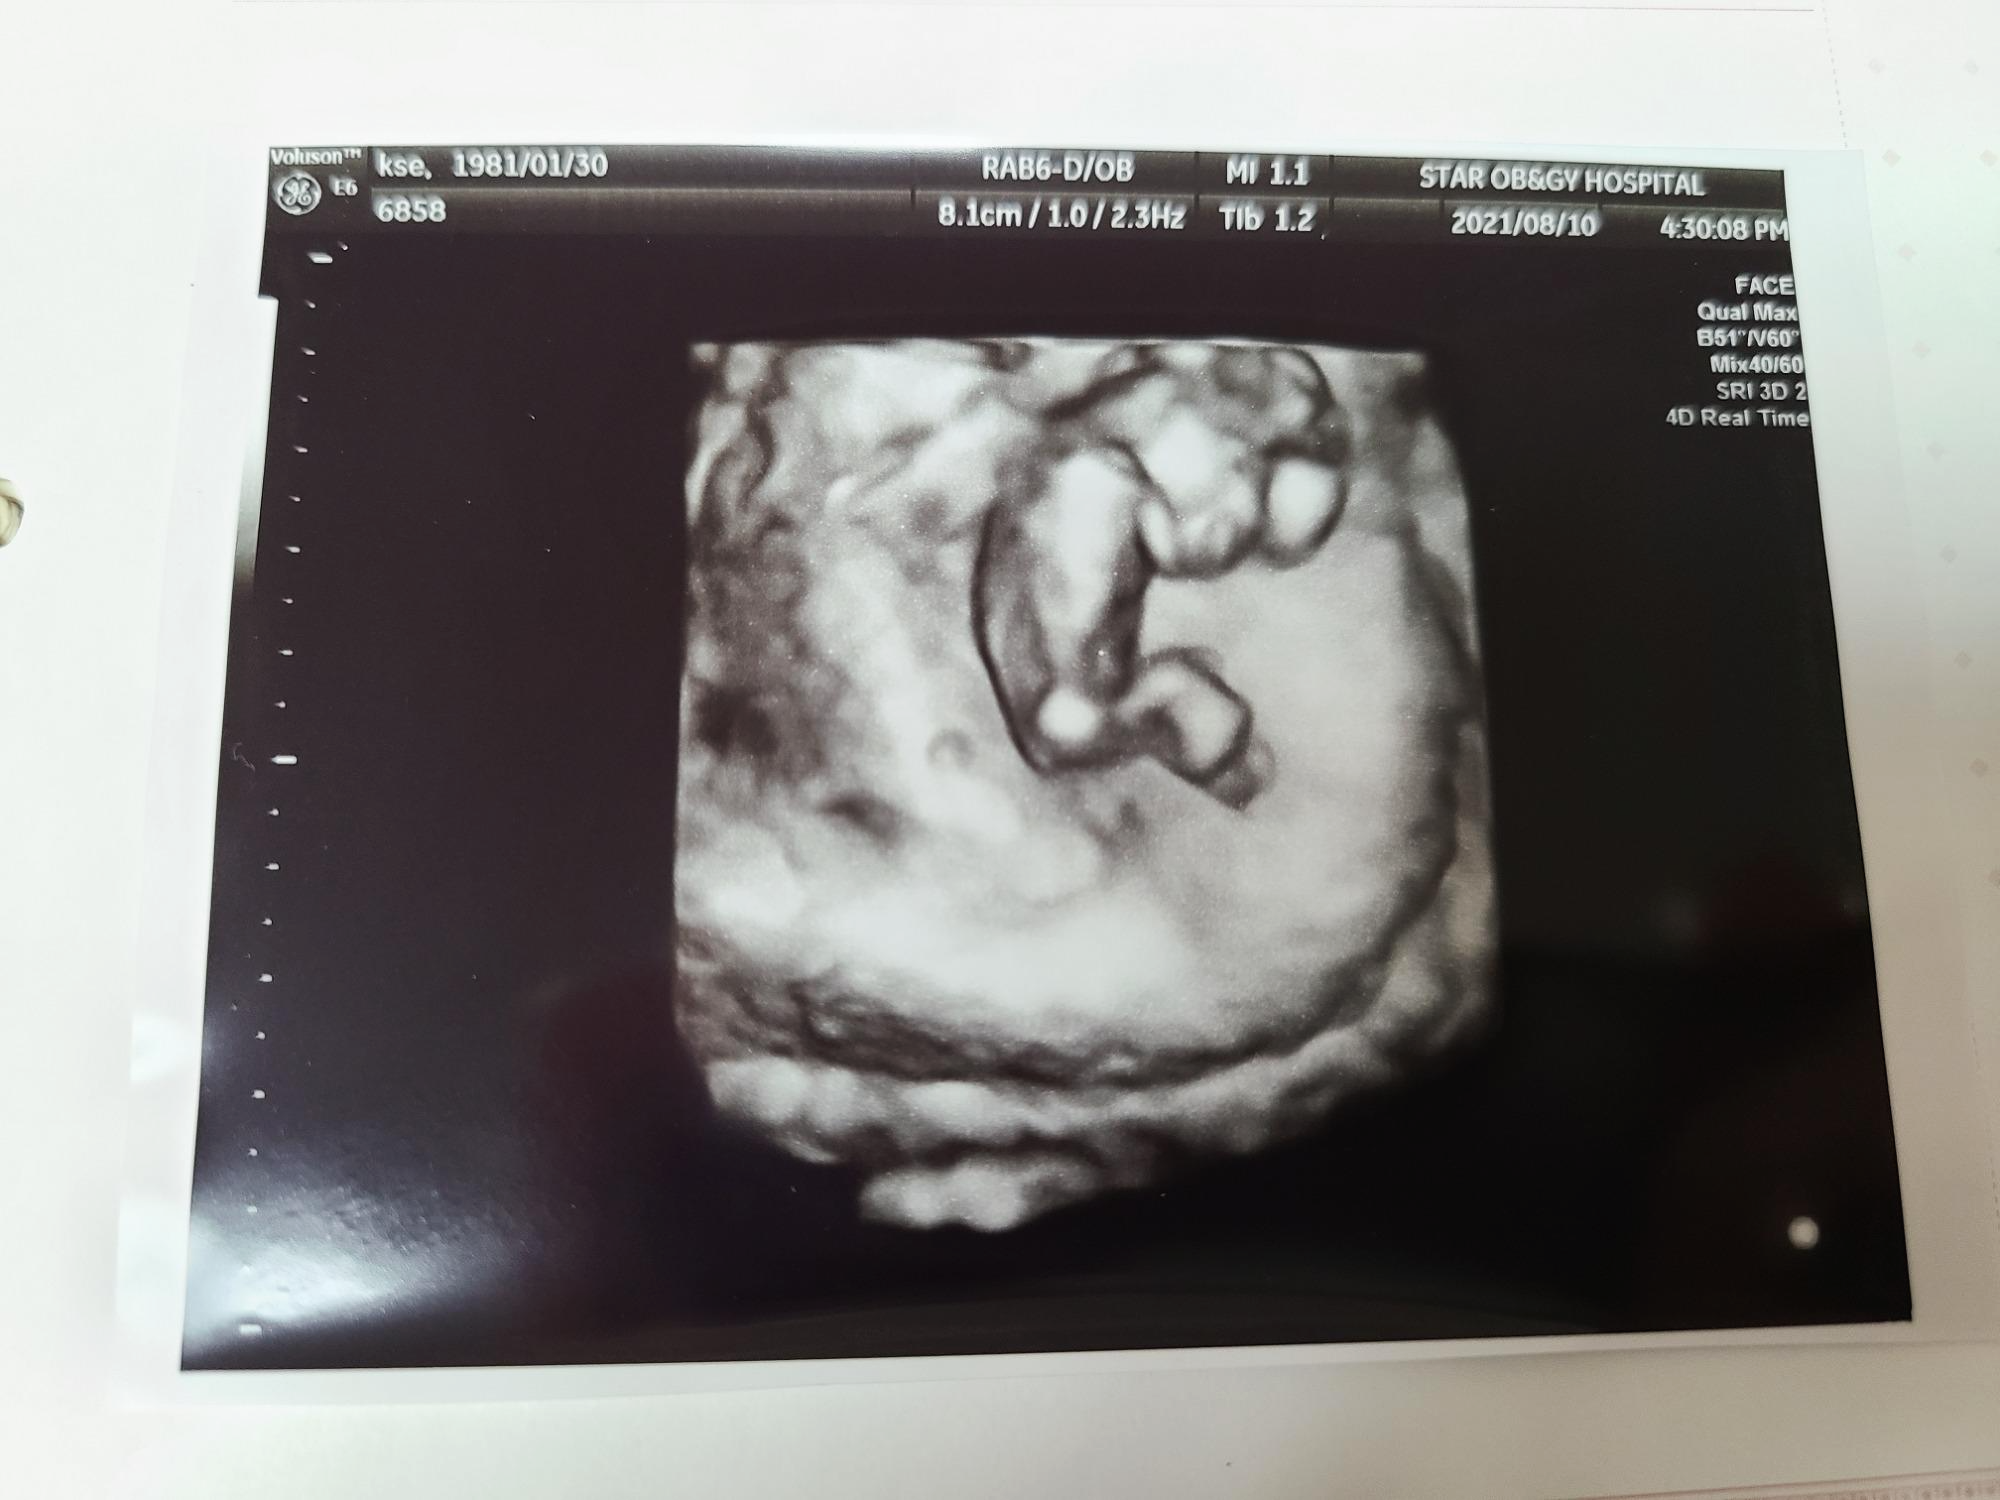

20주에 정밀 초음파를 보며 의사 선생님께서 기형아 검사 결과지를 살짝 화면에 띄워주셨는데 기형아라고 판단할 수 있는 기준점보다 모두 다 낮은 결과가 나왔더라구요.

그 결과를 보고 다시 한번 얼마나 감사하단 생각을 했는지 몰라요.